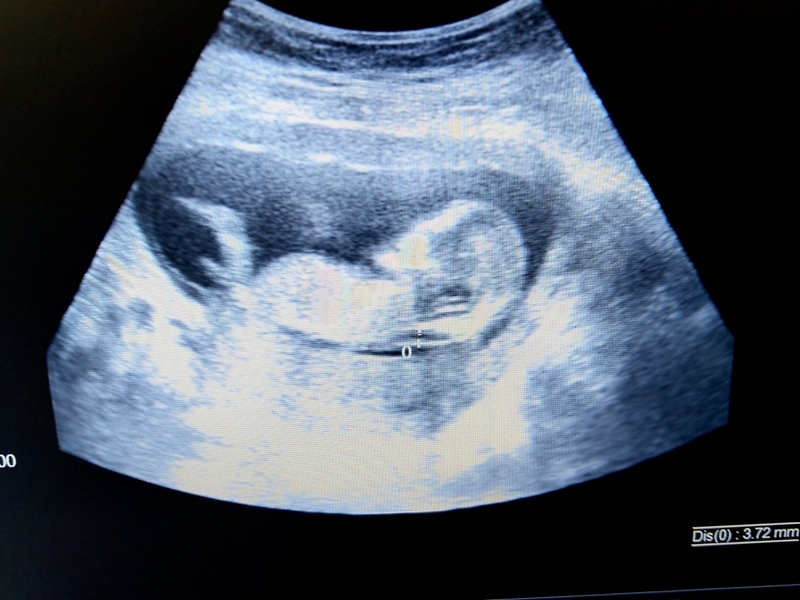

Siêu âm đo độ mờ da gáy hầu như là bắt buộc trong giai đoạn mang thai để phát hiện sớm các bất thường của thai nhi. Vậy, đối với kết quả là 1,5mm thì độ mờ da gáy 1.5mm có bình thường không? Hãy cùng nhà thuốc Long Châu tìm hiểu qua bài viết dưới đây nhé!

Độ mờ da gáy là hiện tượng chất dịch kết tụ ở vùng sau cổ thai nhi. Theo chỉ số này, nguy cơ mắc hội chứng Down và các dị tật khác của thai nhi có thể được xác định. Thường thì việc đo độ mờ da gáy được thực hiện trong khoảng từ 11 tuần đến 13 tuần 6 ngày tuổi của thai.

Đo độ mờ da gáy là quá trình đơn giản khi mẹ bầu đi siêu âm và kiểm tra sức khỏe của thai nhi trong khoảng thời gian từ 11 tuần đến 14 tuần tuổi. Bác sĩ sẽ sử dụng máy siêu âm ở vùng bụng để đo chiều dài từ đỉnh đầu đến cuối xương sống của thai, sau đó sẽ đo độ mờ da gáy.

Trong một số trường hợp, khi thai phụ có vấn đề về cân nặng hoặc tử cung ngả sau, việc đo độ mờ da gáy có thể được thực hiện qua việc đặt dò siêu âm qua âm đạo. Việc sử dụng siêu âm không chỉ giúp xác định độ mờ da gáy để chẩn đoán khả năng dị tật của thai nhi, mà còn cho phép các mẹ bầu nhận thấy sự phát triển và phát hiện các dấu hiệu bất thường của thai nhi để có biện pháp xử lý kịp thời.

Khi sử dụng siêu âm để đo độ mờ da gáy, kết quả có thể đa dạng và phụ thuộc vào kích thước của thai nhi cũng như thời điểm siêu âm được thực hiện. Độ mờ da gáy thường dao động từ 1 đến 3,5mm. Vì vậy, câu hỏi "Liệu độ mờ da gáy 1,5mm có bình thường không?" cần được xem xét kỹ hơn. Để giải đáp thắc mắc này, chúng ta hãy cùng tìm hiểu về mức độ mờ da gáy bình thường.